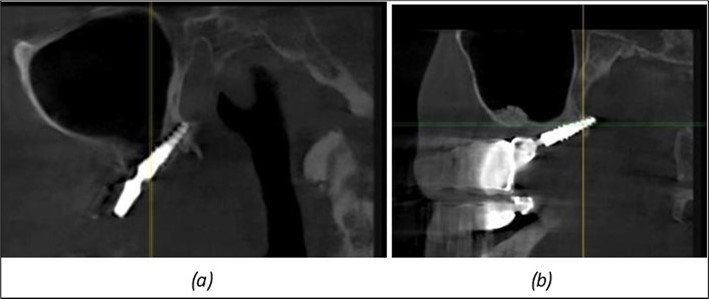

Figure 9.Implants in the pterygoid plateau area: (a) TPG implant fixed in the maxillary-sphenoid junction area, quadrant 1; (b) TPG implant fixed in the maxillary-sphenoid junction area, quadrant 2.

Figure 10.Implants in the palatal sinus cortical area to avoid bone grafting: (a) BCS implant partially fixed in the graft material mass, partially in the palatal cortex; (b) Implant fixed in the palatal cortex at the junction with the nasal cortex, behind the graft material mass.